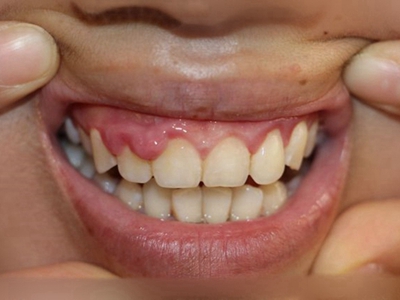

牙龈炎是发生于牙龈组织的炎症,患者可出现牙龈出血伴肿胀、发红、正常形态改变和偶尔不适等症状。本病主要由口腔卫生状况差导致,包括口腔不洁、牙菌斑等,诊断依据临床检查,治疗包括专业牙齿清洁和加强家庭口腔卫生。

牙龈炎可先引起牙齿与牙龈之间的沟(龈沟)加深,然后牙龈充血,炎症围绕一个或多个牙齿,伴牙龈乳头肿胀和易出血。一般无痛,可自行消退,也可维持轻度炎症数年。